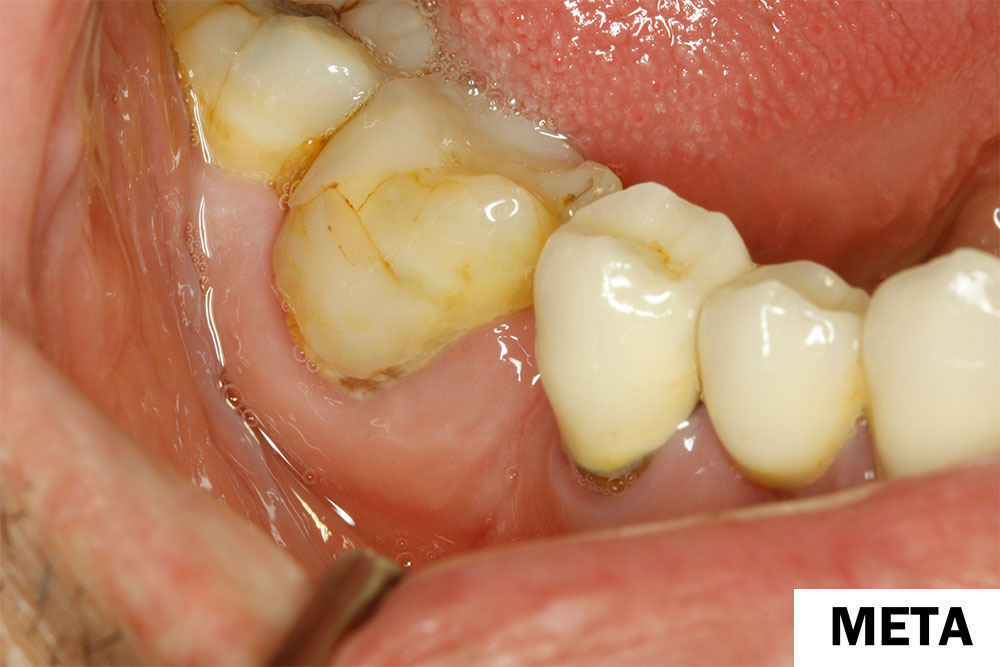

Θεραπεία περιοδοντικού αποστήματος με Laser